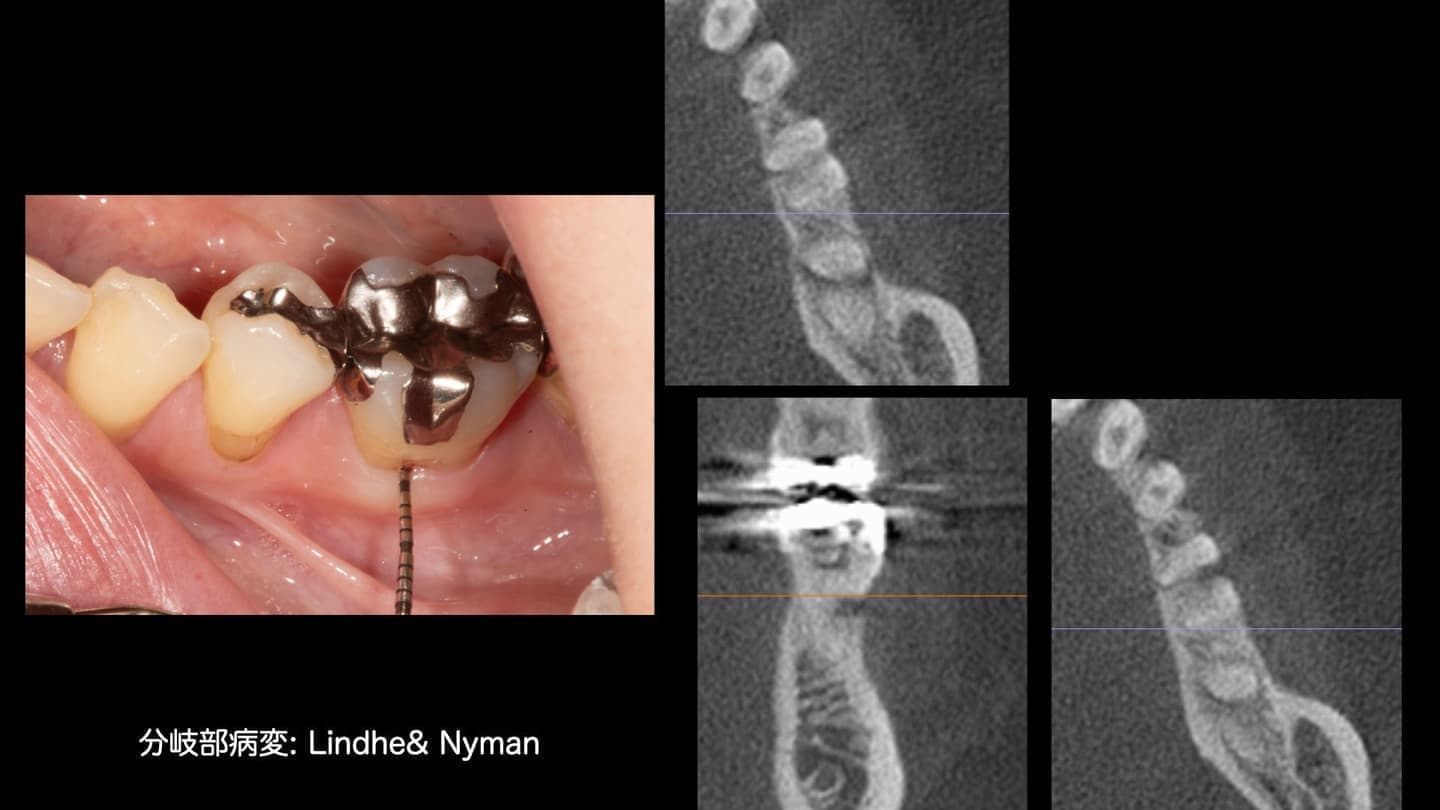

基本的な検査だけでなく、CT検査、歯周病に特異的な細菌のPCR検査、噛み合わせの検査、生活習慣の見直しなどを行います

噛み合わせ、生活習慣などあらゆる原因を調べます

専門医ではないと対応できない症例もあります

指導医として若い専門医への指導も行っています。最新の文献、情報には常に目を通しています

歯周組織再生を基礎研究から生涯のテーマとして取り組んできました